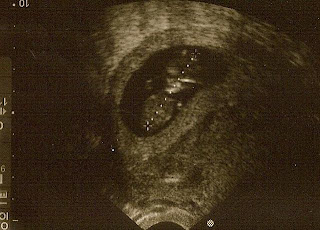

BABY W3 at 10 weeks.

It's official - the Wahrmund's are expanding yet again.  Had an ultrasound today to confirm that A) there is really a baby in there, and B) that I am 10 weeks along.  Just as I had calculated.  Even though I've been sicker than sick for the past five weeks and no doubt indeed expecting, it's always reassuring and wonderful to see the tiny heartbeat and the little flutters of movement (and was he/she really dancing for the camera today!).  I didn't hear the heartbeat at the doctors office, but when I returned home I found the item I ordered waiting for me from Baby Beat, the company that rents out doppler heart beat monitors.  Something I've done with all my pregnancies.  So I immediately checked for the heartbeat and was so excited when I found it!  I could listen to that sound all day long, it is music to my ears.  As of now, all is progressing as it should.  Baby is due June 27....three days before Scotty's 5th birthday!  But since it will be a scheduled c-section, it will be more like June 20.  Sadly, I am now in the "35 and older" category - sometimes referred to as "elderly maternal age".  YIKES!  Hopefully ol' grandma here will be just fine in the coming months.  I'd like to find out the sex of the baby, but Jay, as usual, does not want to know.  He is set to be deployed when baby is born and wants to be surprised via email.  Scotty is excited and is telling everyone about the "baby in mommy's stomach that makes her sick"....both he and Zac pat and talk to my belly.  It really is endearing.  Lets hope that endearment carries over when baby actually arrives :)